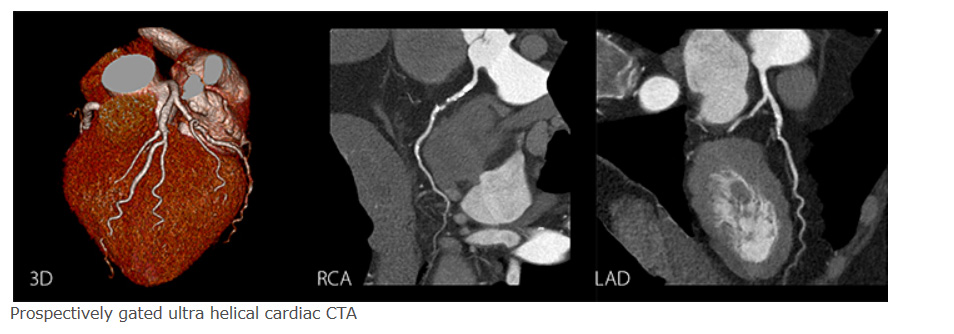

-Prospectively gated ultra helical

Combining the advantages of helical scanning with ECG narrow phase exposure, SURECardio Prospective offers excellent z-axis uniformity, short scan times, and the low-dose advantages delivered by prospective ECG scanning.

SURECardio Prospective:Faster scan for reduced contrast requirements and superior temporal uniformity.